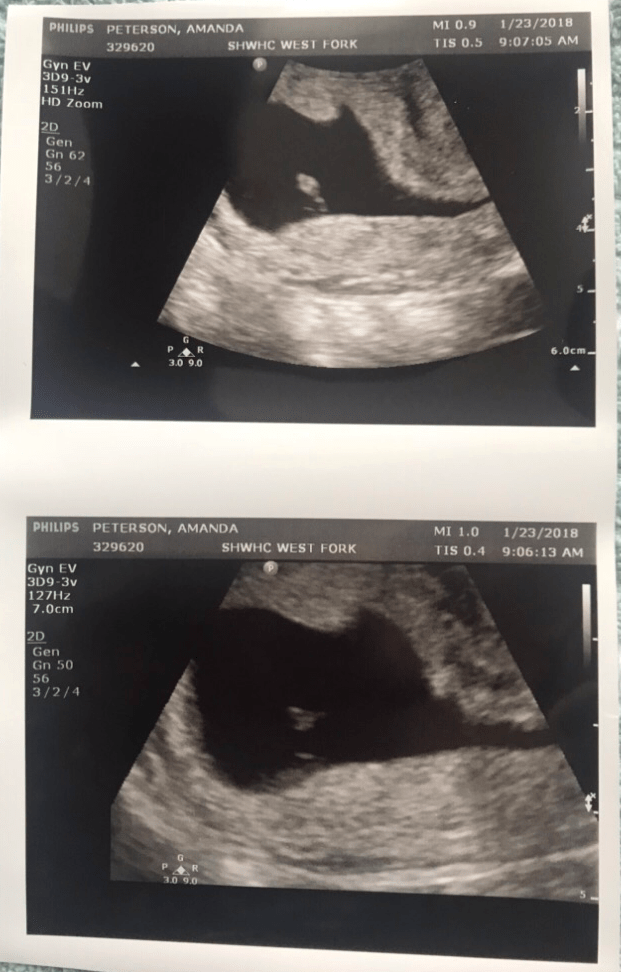

We get started, and she’s moving the probe around for a minute or two when she finally says, “You said you had some bleeding a few weeks ago, is that right?” WHAT THE. Yes, but I called the office the next day and they assured me that since it stopped as quickly as it started, it was nothing to be concerned about. Why in the hell is this the FIRST thing you’re saying to me!?!?!? She follows it with, “Here is your baby. And this little flicker, that’s the heart beat. But, you’re measuring a lot smaller than what you should be at 9 weeks. I’m estimating 6 weeks , maybe a couple days.” We watched for a few minutes while she quickly clicked around on her computer and took photos. “I’m concerned because the sac is shaped irregularly, but Cheyanne (the midwife) will explain the risks.” Click. Computer screen off. Here’s a couple shoddy photos. What just happened???

She leads us to the exam room where we waited for what seemed like eternity for the midwife to come in and speak with us. She, and her medical student assistant nonchalantly said that there is a 50/50 chance that this will be a viable pregnancy. “While there IS a baby, and there IS a heartbeat, the shape of the sac is concerning. Could your dates be off? How regular were your periods?” What, the 3 that I’ve had since I stopped taking my birth control in September? Yeah, no, not regular whatsoever. “Let’s schedule another ultrasound for a week from today and check for growth and changes. In the meantime, if you start to bleed, you can take ibuprofen for the pain, and you should go to the hospital if you are filling more than a pad an hour, or feel dizzy. Do you have any questions?” By this point I’m sobbing and shaking, and unable to speak. Yes, one. Are you assuming I’m going to miscarry?